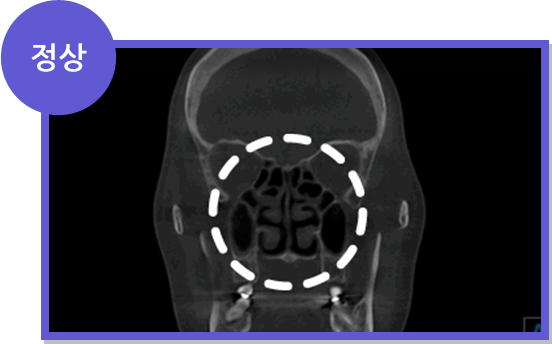

코덧살이 부어오른 만성비후성비염은 고주파를 이용한 간단한 수술이 필요합니다.

비염 CT 정상 소견 비염 CT 비정상 소견